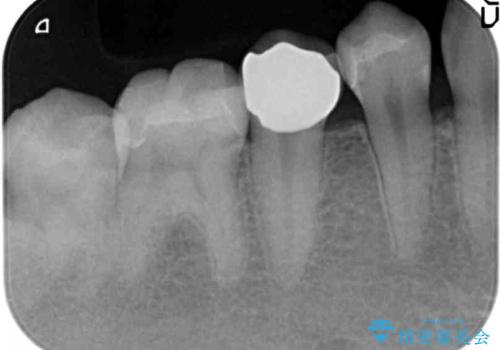

- 以前虫歯治療を行い、詰めた箇所が黒く変色し不安になり検査を求めて来院されました。

X線撮影を行った結果、詰めた箇所の下部に虫歯の再発を認めました。

再発した虫歯は神経に近いことが多く、丁寧に除去することで神経を温存し、精密なセラミック修復を行うことで更なる虫歯の再発を防ぎます。